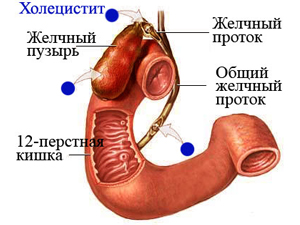

Nem lehet szájon át akut vesebetegség, szív, máj, gyomor-és nyombélfekély, és a gyermekek 12 éves korig.